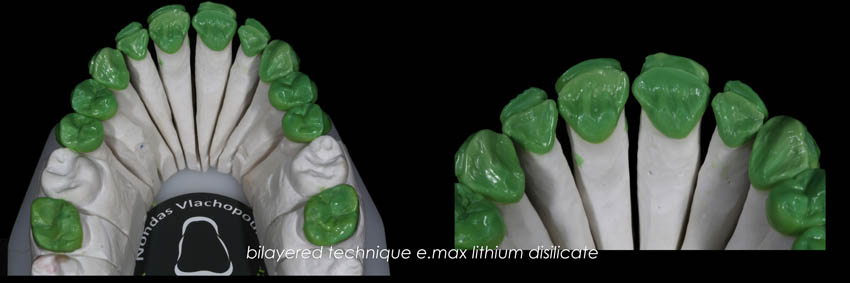

The synergy between digital and analog workflow. When and how?

Materials used in Prosthodontics. What has changed?

Ceramic veneers - materials and step by step clinical procedures

Indications for ceramic veneers and onlays